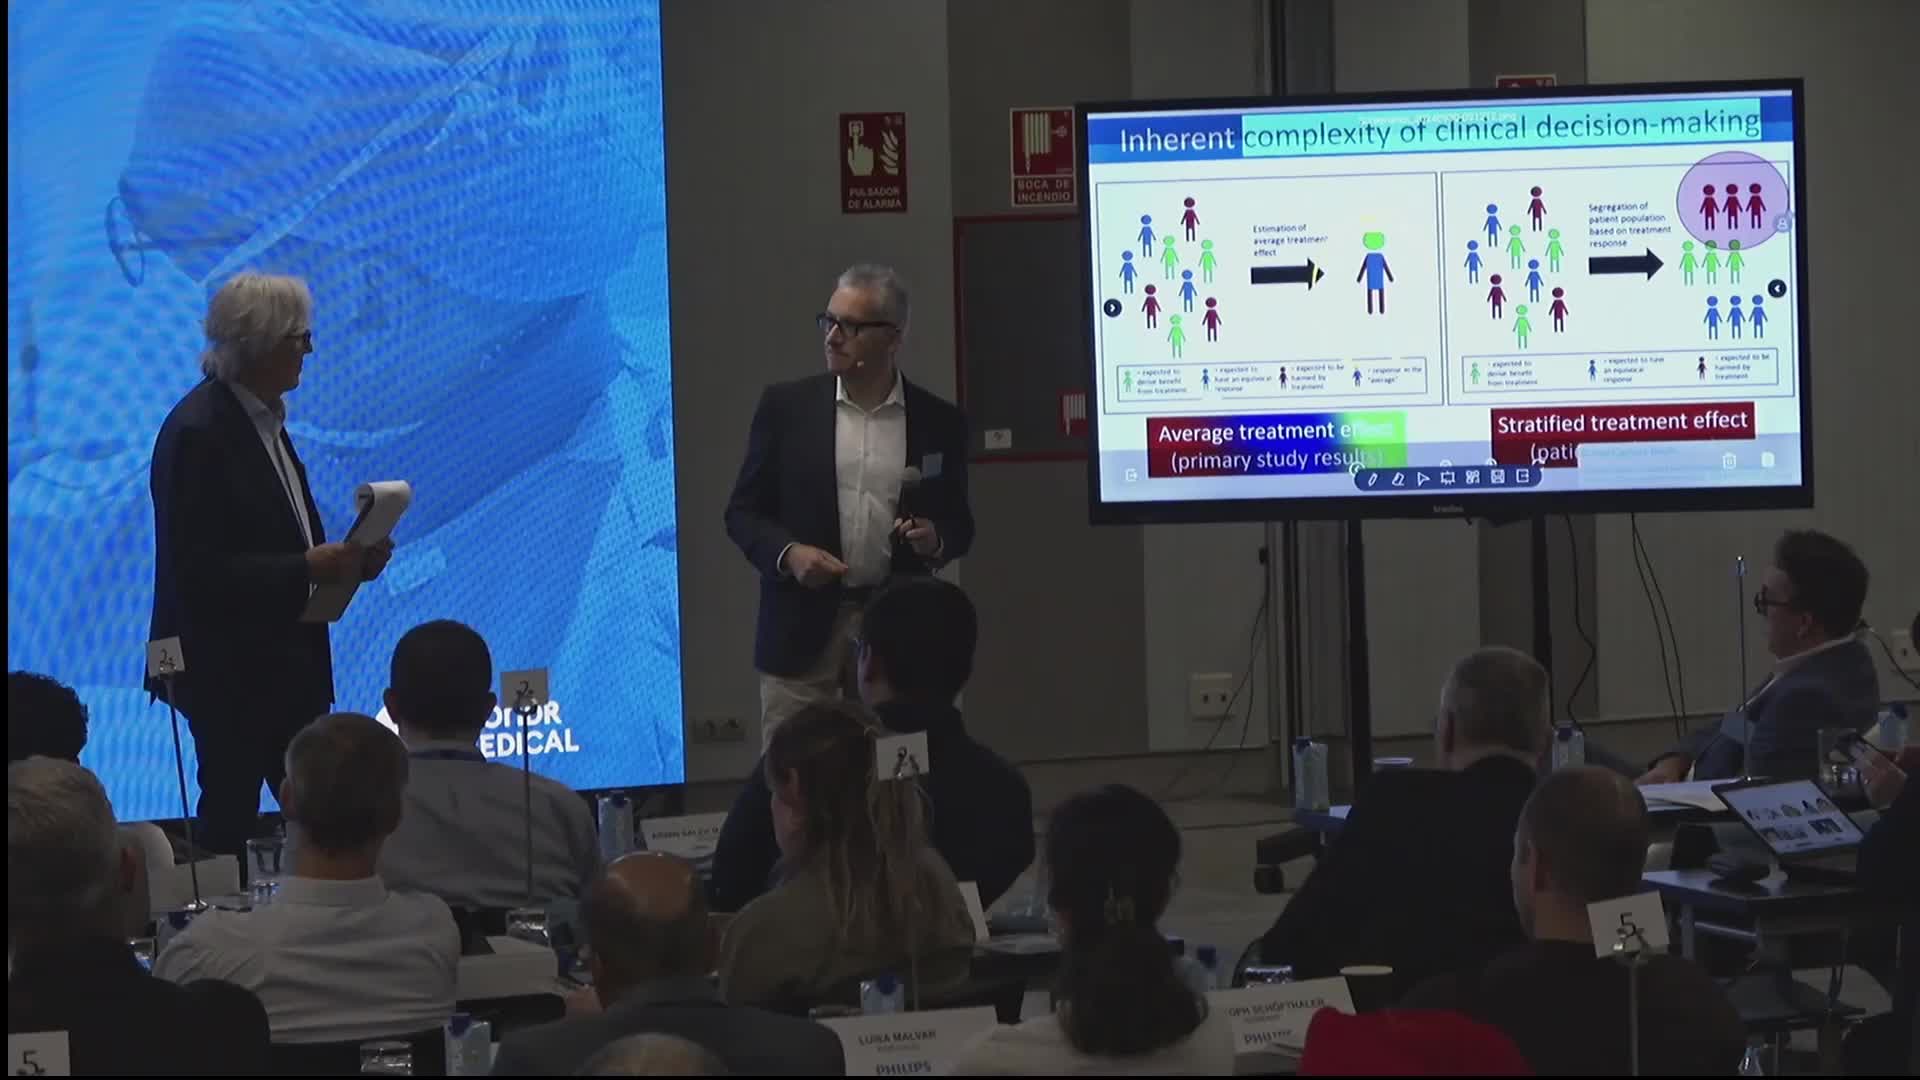

Best practices and personalised medicine in complex PCI - Prof Javier Escaned

Essential steps for physiology-based PCI planning and guidance - Dr Allen Jeremias